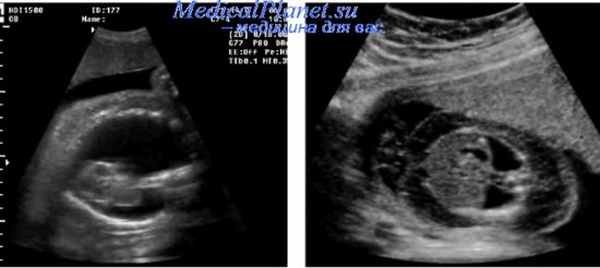

Пренатальная диагностика плеврального выпота основывается на обнаружении скопления жидкости между легкими и стенками грудной полости. Содержимое выпота (хилоторакс или гидроторакс) не может быть точно установлено при ультразвуковом исследовании плода, поскольку эхографическое изображение в обоих случаях одинаково. Более того, даже цитологическое исследование полученной при пренатальной пункции плевральной жидкости не всегда однозначно может интепретировать полученные результаты.